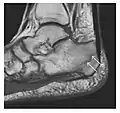

a

b

c

Figure 1: A 56-year-old woman presenting with left knee pain after a fall. (a) Initial anteroposterior radiograph was considered normal, however, subtle cortical disruption of the anterior rim of the medial tibial plateau, medial to the tibial spine, is noted (arrow). (b) Coronal T1-weighted MRI confirms the cortical disruption (arrow) and shows extensive fracture through the proximal tibia. (c) Coronal proton density-weighted image with fat saturation shows extensive edema in the subchondral bone. Note also hypersignal adjacent to the medial collateral ligament corresponding to a grade I sprain (arrowheads).[1]